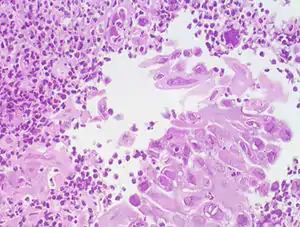

![]() Езофагіт, яки спричинив вірус герпесу Езофагіт, яки спричинив вірус герпесу | |